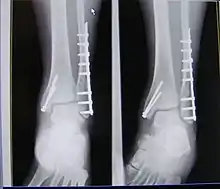

X-ray of trimalleolar fracture repair with plate and nails

Surgical repair using open reduction and internal fixation is generally required, and because there is no lateral restraint of the foot, the ankle cannot bear any weight while the bone knits. This typically takes six weeks in an otherwise healthy person, but can take as much as twelve weeks. Non-surgical treatment may sometimes be considered in cases where the patient has significant health problems or where the risk of surgery may be too great.[1]